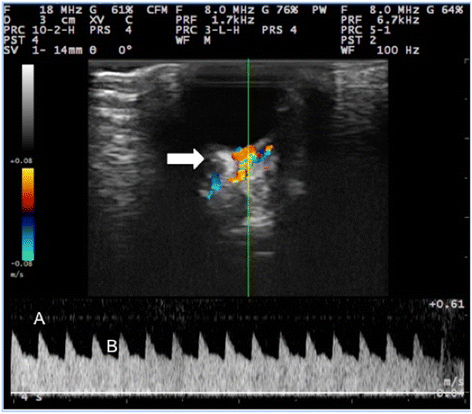

摘要:背景:枸橼酸西地那非可以增加眼部血流量,可用于治疗涉及反射性血管收缩的眼部疾病。因此,本研究旨在确定药物对健康兔球后循环的血管舒张作用。治疗前和治疗后第1天(M1),7(M2),14(M3),21(M4),和30(M5),测量用枸橼酸西地那非或生理盐水处理后的兔眼内压(IOP)、平均动脉压(MAP)、眼灌注压(OPP)和外眼动脉的彩色多普勒成像。结果:治疗组的MAP和OPP值均低于对照组,平均值在M1(S=71.52毫米汞柱,C=84.76毫米汞柱,P=0.0356)和M5(S=71.38毫米汞柱,C=85.52毫米汞柱,P=0.0252)时有统计学差异。眼内压和彩色多普勒值在试验组之间没有差异。结论:10毫克的枸橼酸西地那非给健康兔造成全身性血管扩张,从而降低MAP和OPP值。然而,它不引起眼压和眼球后血流动力学的变化,可通过外眼动脉的彩色多普勒评价来识别。关键词:磷酸二酯酶5型抑制剂 彩色多普勒显像 眼内压 平均动脉压 兔 眼部循环背景:枸橼酸西地那非是第一个磷酸二酯酶5型(PDE-5)抑制剂被批准用于治疗勃起功能障碍,并已成为世界上最广泛的处方药物之一。该药物抑制PDE5、水解环磷酸鸟苷(cGMP)的酶,调节cGMP的循环水平,进而导致阴茎海绵体肌松弛和局部血流量增加。然而,PDE5不仅存在于阴茎海绵体中,还存在于周围动脉和静脉平滑肌细胞中,也存在于肺和冠状循环、血小板和血管内皮细胞中。因此,PDE5抑制剂药物可引起全身血流动力学改变。虽然该药物广泛用于治疗勃起功能障碍,但一些使用者表现出视觉副作用,例如视力模糊和对光的敏感性增加。这些症状与存在于视网膜中的磷酸二酯酶6型药物的交叉抑制有关,参与光传导机制的调控。然而,关于枸橼酸西地那非抑制视网膜和球后血流抑制这些区域血管壁中PDE5的作用尚未达成共识。识别和量化由枸橼酸西地那非引起的球后循环中的血管舒张活性可以提供重要的临床信息,特别是对于患有眼反射性血管收缩条件的患者,如肾衰竭患者视网膜高血压。慢性高血压导致视网膜小动脉的持续代偿性血管收缩,引起缺血和视网膜变性,损害了该组织的功能。考虑到枸橼酸西地那非治疗具有反射性血管收缩的眼部疾病的潜力,本研究的目的是基于眼部灌注压力的评估和外眼动脉的彩色多普勒成像,确定药物是否具有血管扩张剂对健康兔眼球后循环的影响。方法:动物和实验设计:本研究对健康成年雄性新西兰白兔14只,平均体重2.5 kg。样本量基于获得可靠统计结果所需的数量。兽医进行临床检查后,动物的眼睛和总体健康被认为是正常的。兔单笼饲养,自由采食和饮水,温度24±1°C。将兔分为两组,每组七只(n=7),对照组(C)和治疗组(S)。组(C)口服1.5毫升盐水,对照组口服枸橼酸西地那非10 mg。两组均按24小时间隔进行治疗连续治疗30天。实验方案:(1)口服西地那非扩血管剂,(2)测量眼内压(IOP),(3)测量平均动脉压(MAP),和眼外动脉的彩色多普勒超声成像。口服枸橼酸西地那非,在摄入药物和后续步骤之间允许45至60分钟的等待时间。每周进行一次评估:第一天(M1),第七天(M2),第十四天(M3),第二十一天(M4),和第三十天(M5)。测量IOP和MAP和多普勒研究,未经镇静的兔子被裹在毛巾中,只留下头部供研究者测量。在评估期间,不采取过度的力量来限制动物。为了减少节制期,仅对每只动物的右眼进行检查,从而避免应激对球后循环的影响,并优化药物的作用时间。眼内压测量:用Too-PoN AVAS VET?压平眼压计测量兔眼压。该程序包括轻轻抬起眼睑,在眼睛上滴下0.5%丙美卡因,五分钟后用眼压计进行测量。MAP测量:在兔耳背侧表面切开和防腐后,用24G导管插管中心动脉。然后将导管插入半刚性硅胶管系统。在该系统中,两个硅胶管连接到三通旋塞阀上。一个管的自由端用导管固定,另一端用BD血压计。然后用1毫升肝素/ 1000毫升0.9%盐水填充该系统。空气/液体界面位于右心房和眼的高度,用血压计读平均动脉压。OPP计算:眼灌注压(OPP)是通过眼内压(IOP)减去平均动脉压(MAP)来确定的,如Kiel& Huvin所描述的。彩色多普勒显像:使用Mylab的30兽医超声系统耦合到13 - 18 MHz线性换能器进行外眼动脉的彩色多普勒评价。检查前,滴注0.5%滴盐酸丙美卡因局部麻醉剂麻醉角膜。然后将无菌水性凝胶层涂抹到角膜表面,并将传感器轻轻放置在纵向位置,位置指示器面向上眼睑。用二维模式记录眼球和视神经的矢状面图像。用彩色多普勒超声观察眼外动脉在视神经入口附近的位置。然后将脉冲波多普勒的光标立即定位在眼腔动脉上,用均匀的声发射方法记录血管腔内的血流曲线,在此基础上用该曲线评价峰值收缩速度(PSV)和舒张末期速度(EDV)。未校正角度,测量不大于60°。根据PuleloT方程(Ri=PSVαEVS/PSV),用Mylab软件自动计算眼部动脉阻力指数(RI),并用同一算子(APAC)对其曲线进行分析,对三个连续曲线的PSV和EDV进行了标记。统计方法:采用随机2×5裂区试验设计,用相应的处理(有和不含枸橼酸西地那非),评估M1-M2-M3-M4-M5,从每一只动物到一个实验组。使用R?统计软件,通过Shapiro-Wielk检验对数据进行正态性检验,并进行方差分析。用TUKEY检验方法进行比较。结果:眼灌注压:两组平均基线IOP、MAP和OPP值分别为11.85毫米汞柱、80.71毫米汞柱和68.85毫米汞柱。在实验条件下,组(S)的MAP和OPP值较对照组(C)在M1(S=71.52毫米汞柱,C=84.76毫米汞柱,P=0.0356)和M5(S=71.38毫米汞柱,C=85.52毫米汞柱,P=0.0252)时有统计学差异。然而,IOP值在实验期间没有统计学差异。彩色多普勒显像:治疗前,两组家兔右眼外眼动脉彩色多普勒观察的平均基线值为22.99 cm/s,EDV为12.29 cm/s,阻力指数为0.53。眼外动脉在彩色多普勒中显示出红色血流,表现为具有中等电阻率、二色性和存在两个峰值收缩速度的层流模式。但在实验条件下,试验组的彩色多普勒超声值无统计学差异。讨论:本研究发现枸橼酸西地那非降低了家兔的平均动脉压。在人类中,这种药物也被发现在摄入后一小时引起收缩压和舒张压显著降低。然而,其他研究发现,在服用该药后,人体血压没有变化。尽管MAP在M1和M5时刻显著降低,但是治疗的动物没有低血压,因为该物种的正常血压范围从70毫米汞柱到170毫米汞柱。结论:根据本研究中获得的数据,可以指出,剂量为10mg的西地那非给健康兔造成全身性血管扩张,降低其平均动脉压和眼灌注压。然而,该药物不会引起眼球外动脉血流动力学变化,也不会改变眼压。